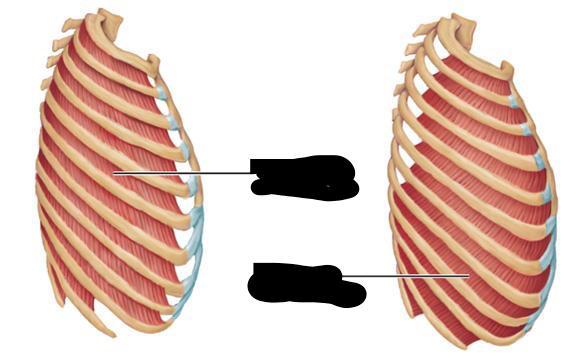

Internal/external intercostal muscle